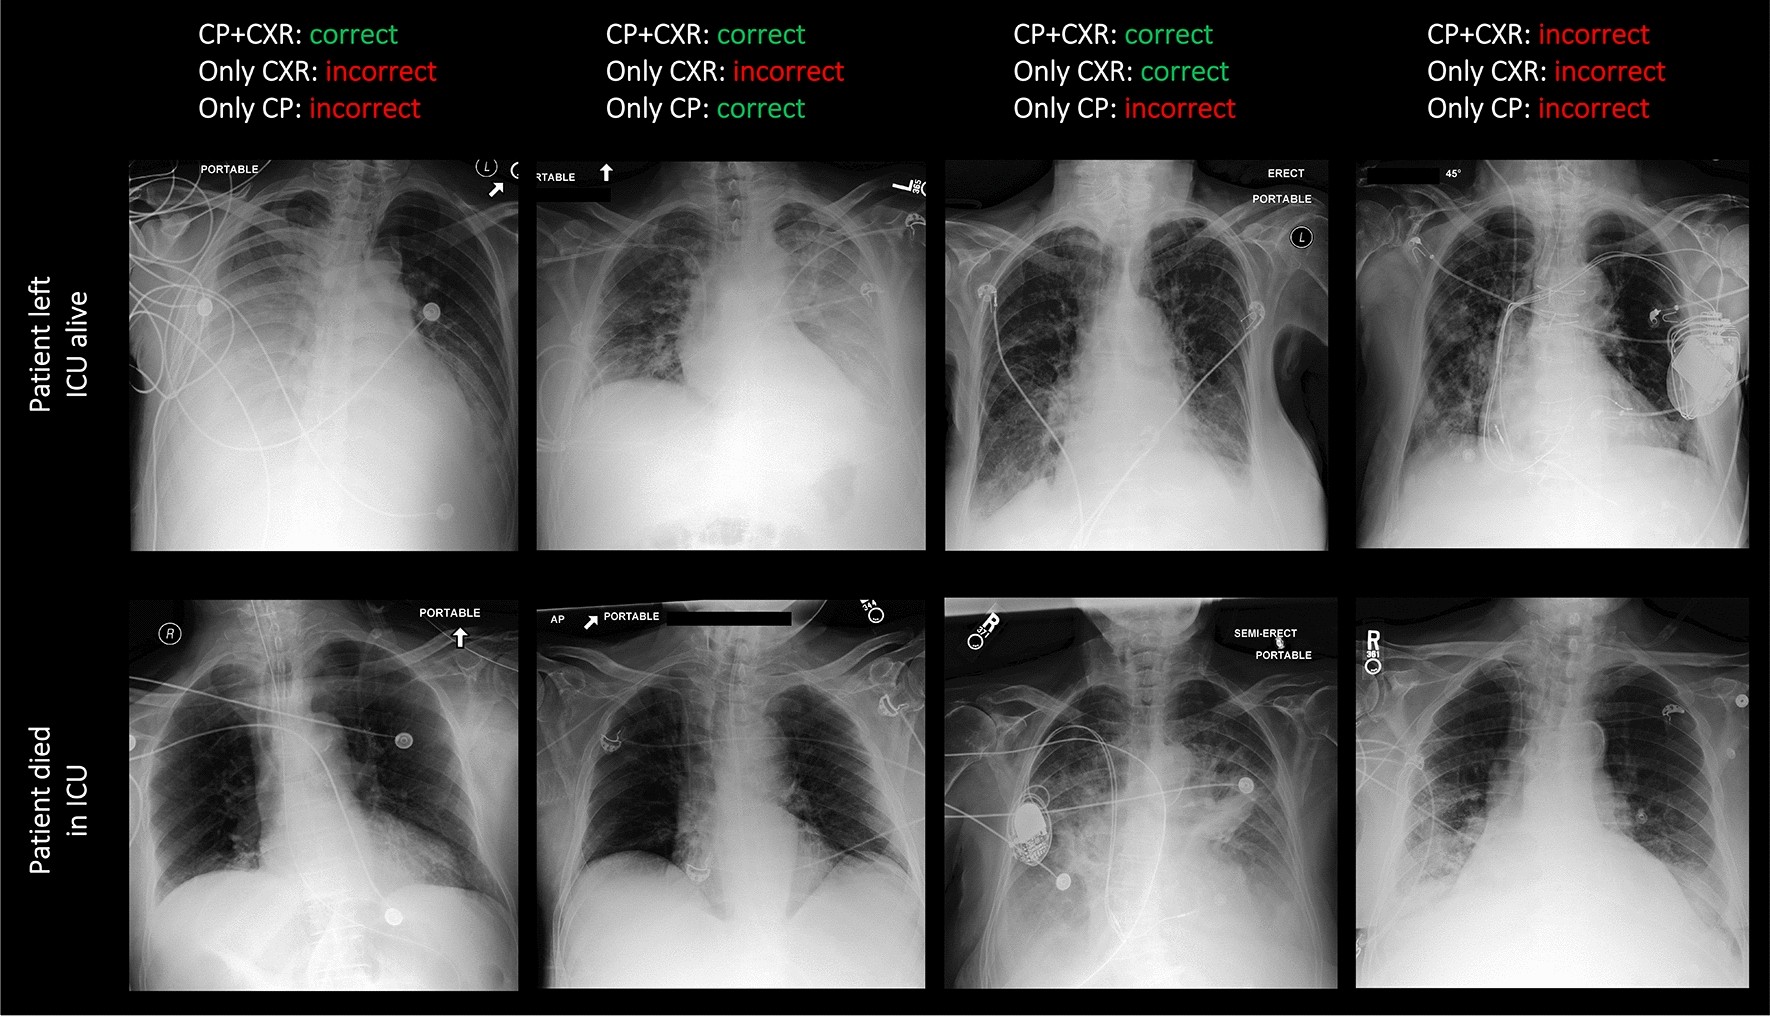

Figure 3

Exemplary chest radiographs and associated patient survival predictions. The upper row shows chest radiographs of four patients dismissed from the ICU alive. The lower row shows chest radiographs of four patients who died in intensive care. Predictions of the model were

depending on whether all data, i.e., imaging and non-imaging data (“CP + CXR”) was provided, or whether only the imaging data (“Only CXR”) or only the clinical parameters (“Only CP”) were provided. Please refer to Fig. 2 for an explanation of the abbreviations.